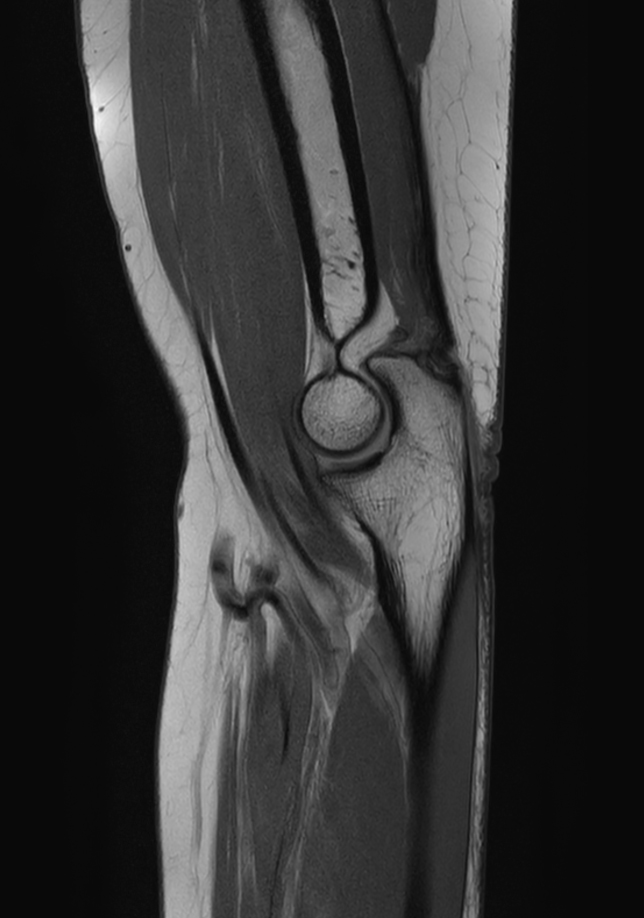

Large FOV imaging with the dS 16ch Small Extremity coil

Used Solution

• System

• Coil

• Clinical Application